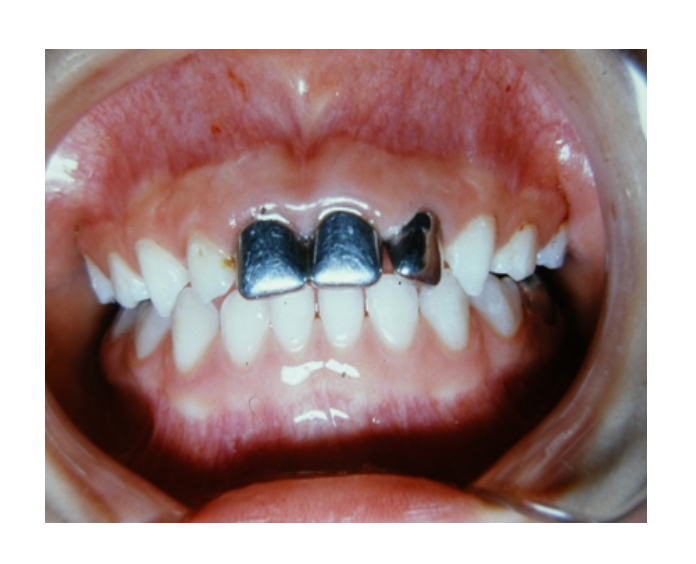

Prótesis fija de zirconia

sin metal